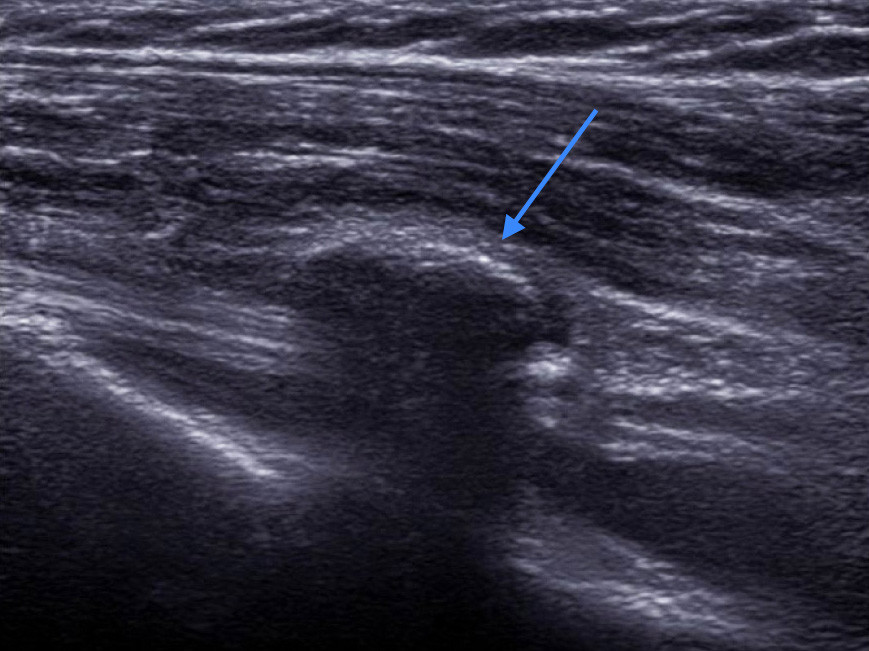

Diese Bild zeigt ein Gelenksganglion am Ellenbogen (Pfeil). Es sieht aus wie ein Ball und der Ultraschall geht komplett durch das Ganglion durch.